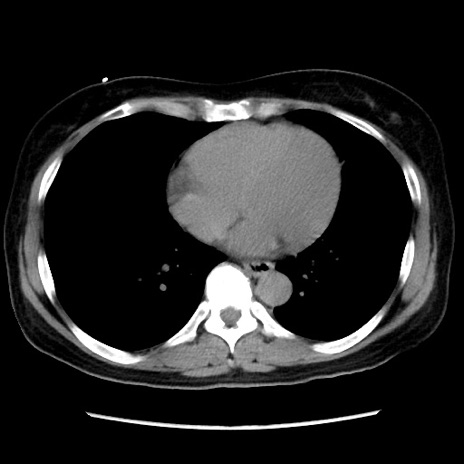

症例10(横断像)

【症例】 50歳代女性

【主訴】 腹痛

【現病歴】前日生レバーを食べた。今朝に排便あり。 昼前に突然発症の腹痛を生じ、当院救急外来を受診した。

【既往歴】 子宮筋腫にてで子宮全摘後

【身体所見】 意識清明、腹部:平坦、軟、下腹部やや左を中心に圧痛・反跳痛あり、筋性防御あり

【データ】WBC 7800、CRP 0.07